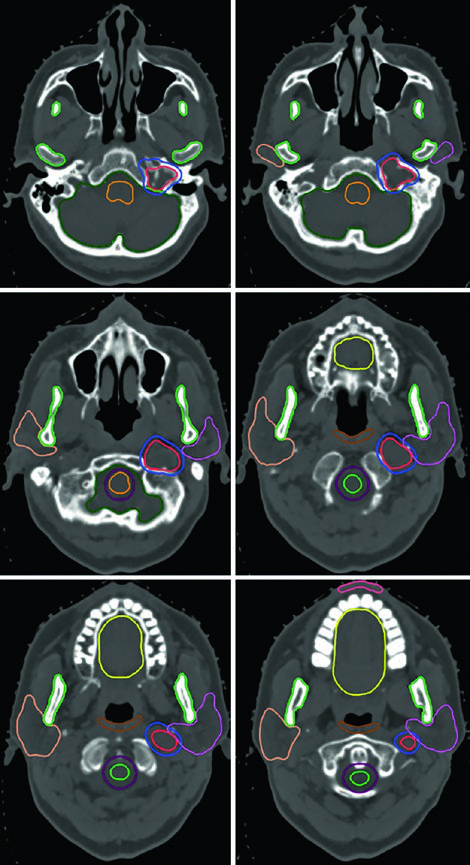

O adenoma secretor de GH da Figura 29.11 demonstra tratamento com SRS a 24 Gy. O tumor toca a margem medial da carótida cavernosa e se estende lateralmente entre as alças da carótida, com envolvimento do seio cavernoso. A dose ao quiasma, nervos ópticos e tronco encefálico permaneceu abaixo de 8 Gy. Na Figura 29.12, o adenoma não secretor mostra invasão do seio cavernoso direito e extensão suprasselar — após ressecção, o tumor residual na sela e no seio cavernoso persistiu.

A Figura 29.13 mostra o planejamento fracionado do mesmo paciente: GTV em coral, CTV com margem de 0,5 cm anatomicamente restrita em teal, PTV com expansão adicional de 0,3 cm. Tronco encefálico, quiasma e nervos ópticos aparecem como OARs delineados. Para macroadenomas, quando a invasão do seio cavernoso é difícil de visualizar, a recomendação é incluir o seio cavernoso inteiro no GTV. Conhecer o tipo de material implantado na sela (músculo, gordura ou retalho de septo nasal) ajuda a diferenciá-lo de tumor residual.